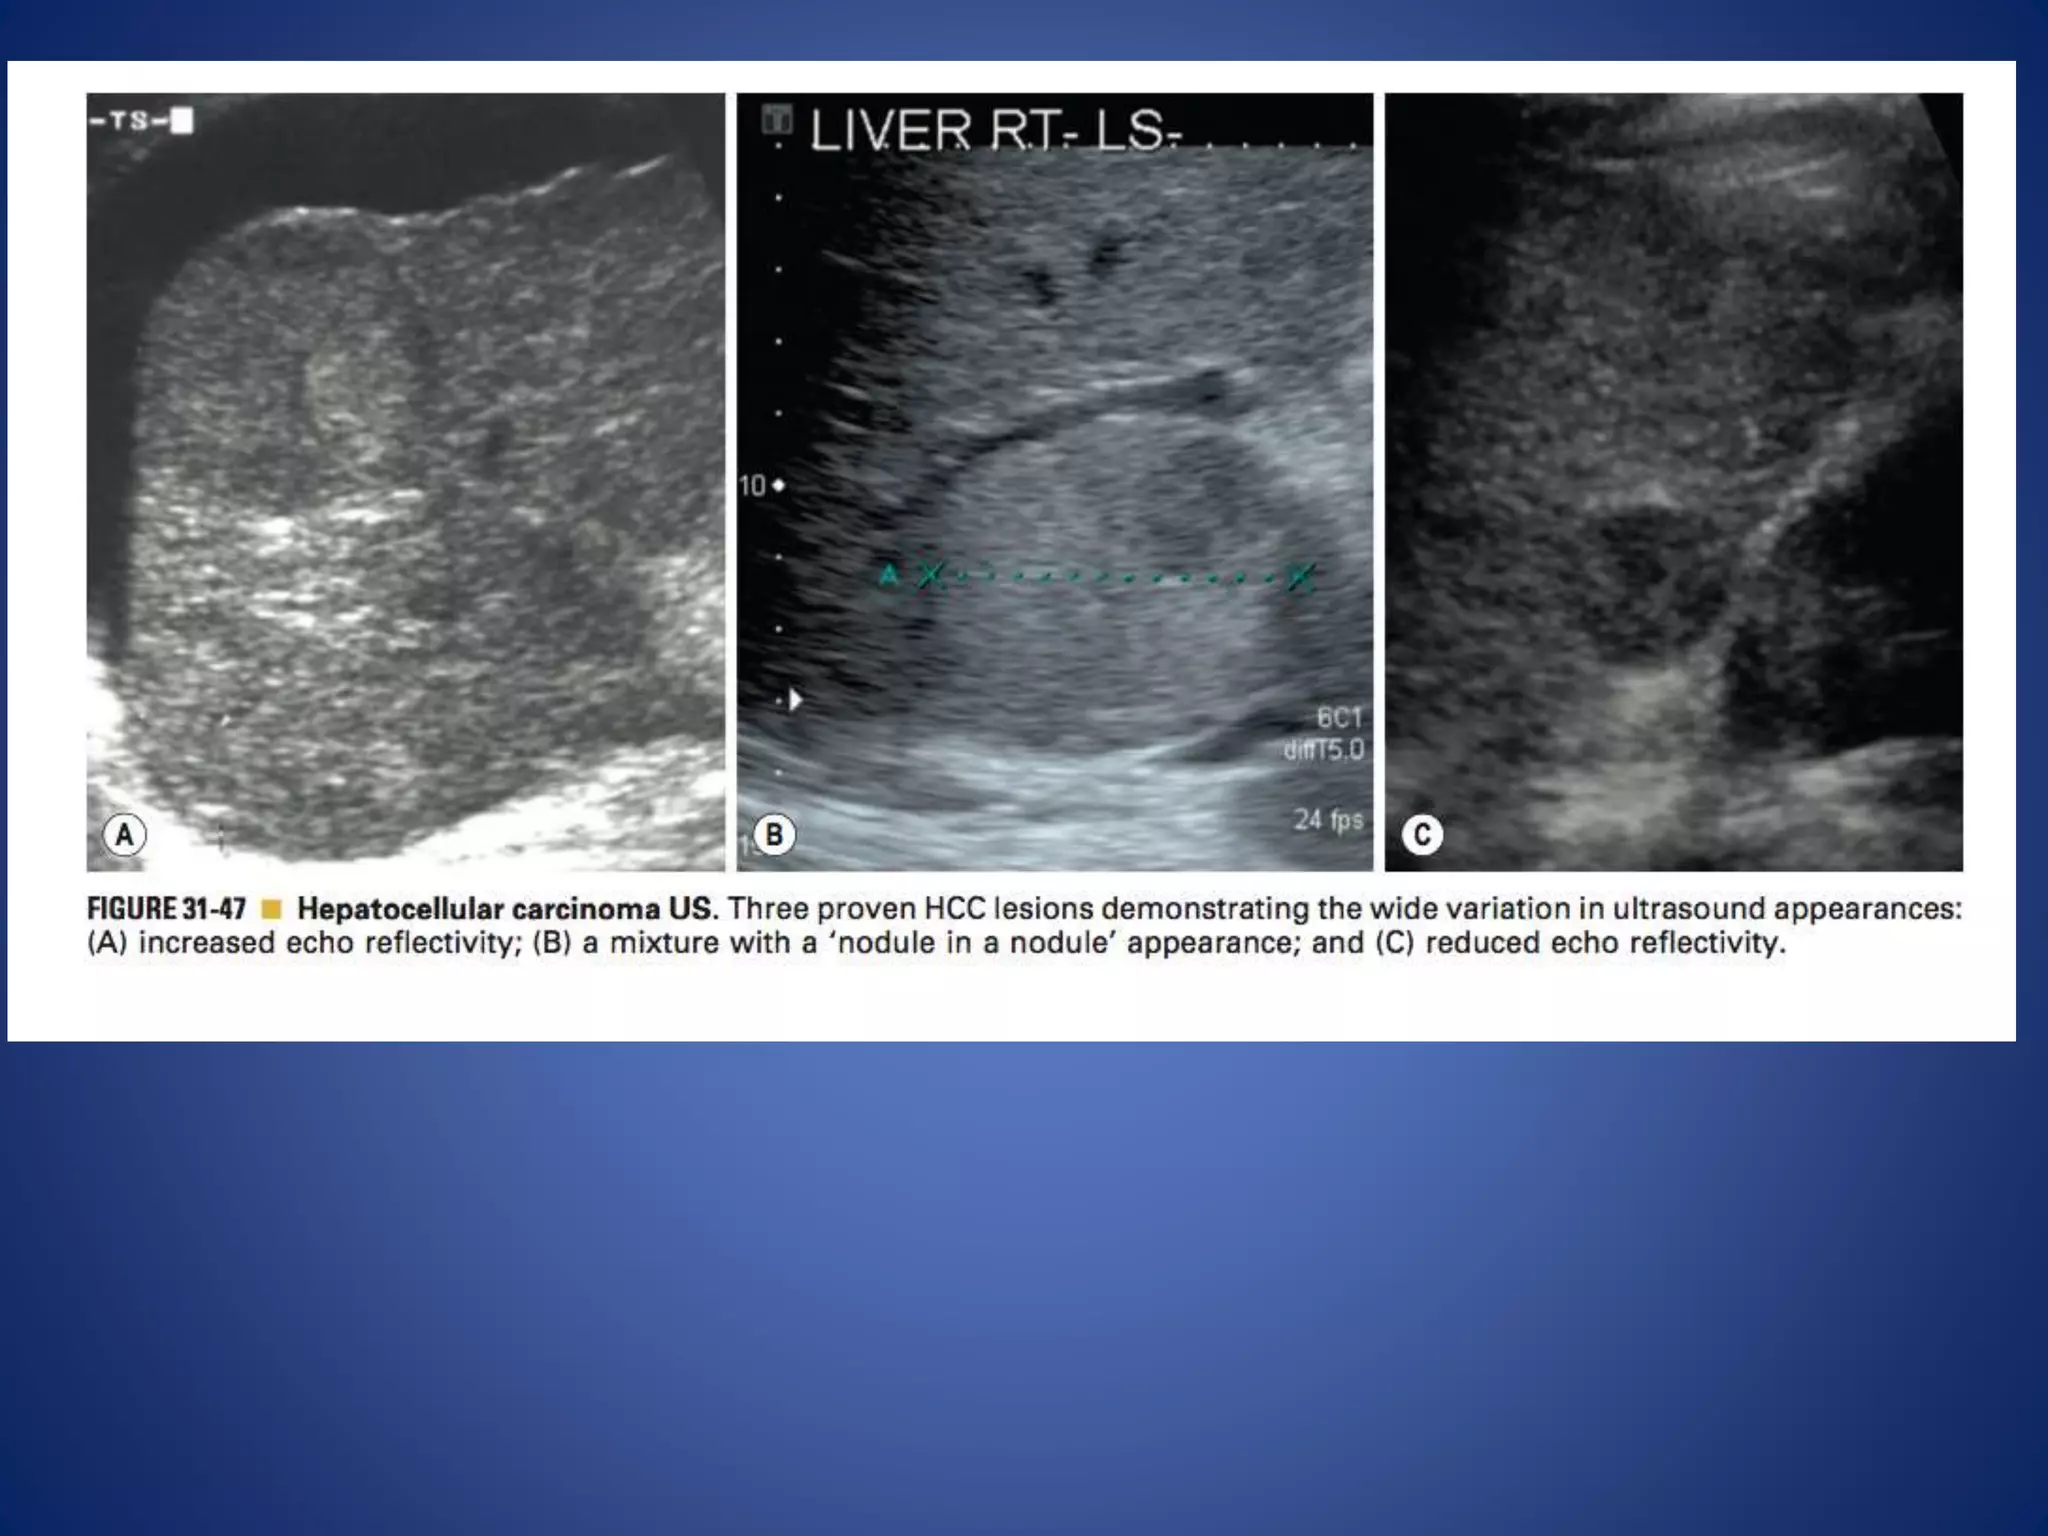

This document discusses various malignant liver lesions including hepatocellular carcinoma (HCC), liver metastases, and angiosarcoma. HCC is the most common primary liver cancer, often occurring in cirrhotic livers, and can appear solitary or multifocal on imaging. Liver metastases commonly spread from gastrointestinal or non-gastrointestinal primary cancers via the hepatic artery or portal vein. Angiosarcoma is a rare malignant vascular liver tumor associated with toxins like polyvinylchloride and arsenic.